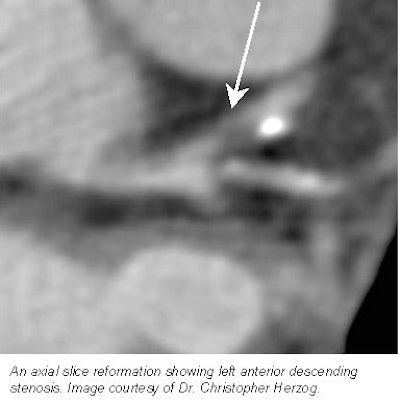

Each patient’s CT data set was then examined using four different visualization techniques: axial, multiplanar, 3-D, and virtual endoscopy. The data set visualization was conducted on four independent workstations. The axial images were reconstructed on a Somatom Plus 4 Volume Zoom workstation using a 512 x 512 matrix and a slice thickness of 1.25 mm.

The highest sensitivity for the evaluation of stenoses, 66.7%, was achieved by the axial reconstructions, Herzog said. Virtual endoscopy had a sensitivity of 55.9%, multiplanar reconstructions, 46.6%, and 3-D reconstructions, 33.3%.